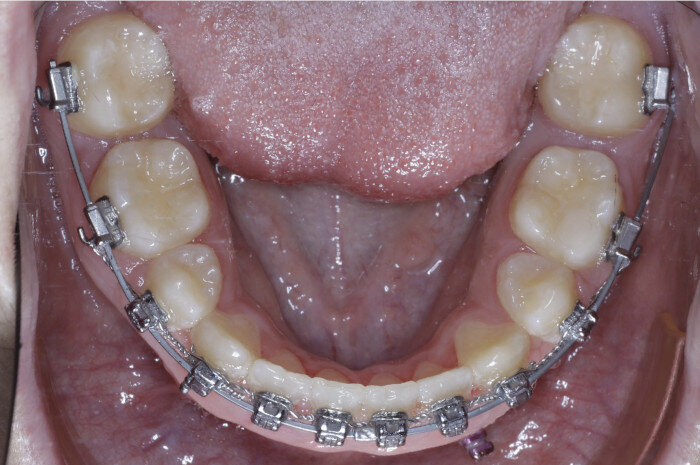

In cases where the deep bite consists of overeruption of teeth #43–33, two TADs are placed (1.6 × 6.0 mm) between tooth #42 and #43 and between tooth #32 and #33 to aid in opening the bite (Figs. 36–39).